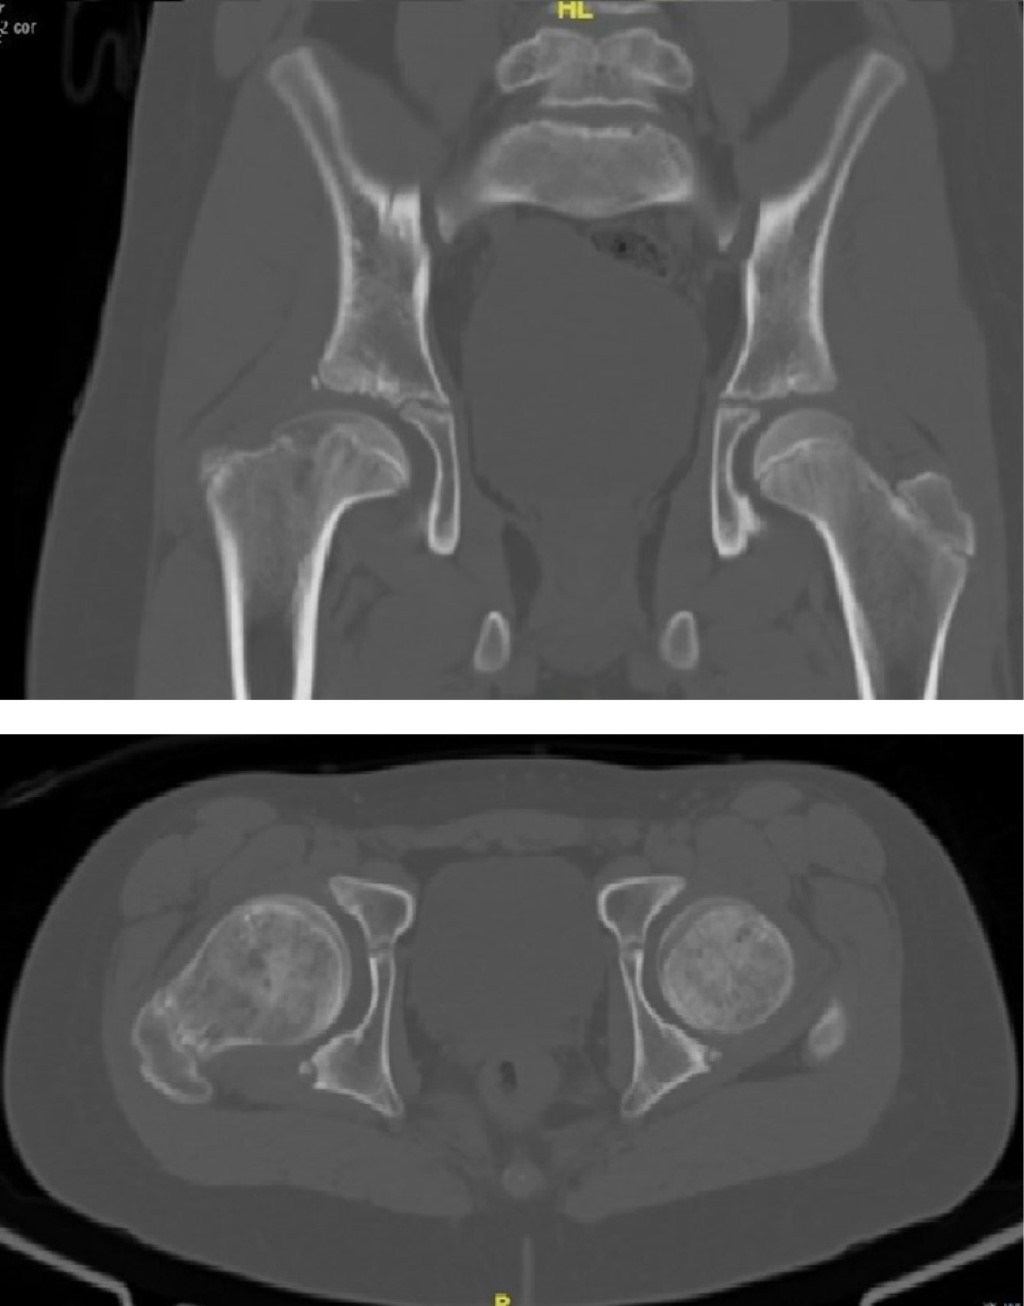

Treatment of femoroacetabular impingement with controlled dislocation of the hip

The femoroacetabular impingement is a syndrome caused by abnormal contact between the femoral head and the acetabulum; it can progress in complications, and the treatment must be individualized with the aim to restore the functionality of the joint. A case of a 12 years old patient who presented clinical findings about impingement, he has history Perthes disease. We performed a surgical hip dislocation technique with femoroplasty. We obtained good results. The clinical and radiographic characteristics of the patient has described and the case resolution.

Figure 4